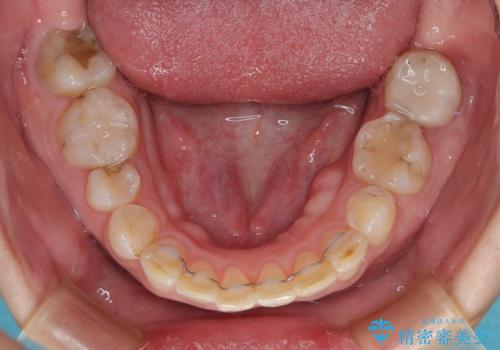

歯の動きが鈍く、矯正治療だけで4年以上の期間を要することとなりました。

矯正治療後は、気になっていた銀歯を全てセラミックとし、きれいな口元に仕上げることができました。

- 矯正治療後の保定が不十分だと後戻り(元の位置に戻ろうとする動き)をします